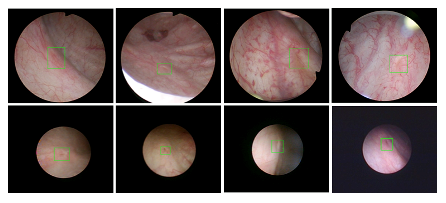

beat365中国唯一官方网站医疗机器人研究院—深睿医疗人工智能医学视频联合实验室成立于2018年7月。PI包括来自于交大生医工学院和电院的三位教授,平台建设目标是将人工智能实时地用到临床医学中去,研究方向包括:1. 建立内窥镜人工智能辅助诊断系统,通过对病灶和解剖结构的实时识别来辅助医生更好地进行微创诊断和治疗;2. 以个性化、定量化的精准诊疗技术为研发目标,重点开展医学影像智能诊断、医学可视化及计算机辅助手术规划、AI及大数据分析在临床诊疗流程中的集成应用等方向的研发。试图利用AI技术、大数据分析技术、3D打印技术、虚拟现实及增强现实技术促进临床的影像诊断、治疗方案设计、预后预测分析等诊疗环节的智能化提升与技术变革;3. 面向运动医学康复、神经退行性疾病量化诊断,以及其他与人体运动相关的疾病诊疗、康复应用,开展视觉三维人体运动的测量、分析与识别研究,通过基于深度学习的视觉检测识别以及相关大数据分析,为相关疾病的诊疗和康复提供AI辅助。具体临床应用包括:关节镜手术术后康复指导和评估、帕金森病的量化诊断、精神疾病的量化诊断与评估、儿童异常行为分析等。

近年来,联合实验室发展了泌尿镜手术实时识别技术,人体姿态精确识别技术,另外围绕小儿先心病手术、肝癌消融手术、数字口腔诊疗的智能化提升等内容进行应用研发。